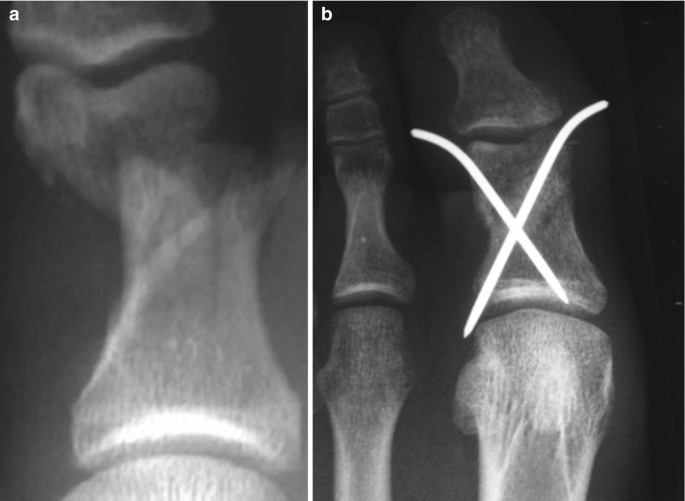

병원에서는 우선 X-ray 촬영을 통해 뼈의 어긋남 여부를 확인한다. 단순 골절이라면 부목 고정이나 깁스로 충분하지만, 뼈가 틀어졌거나 조각난 경우에는 정복술 또는 핀 고정 수술이 필요하다. 치료 과정은 다음과 같이 진행된다.

- 정복: 뼈의 위치가 어긋난 경우, 국소마취 하에 제자리로 맞춤

- 고정: 부목, 깁스, 테이핑으로 3~6주간 고정

- 수술: 금속 핀, 나사, 철심을 이용한 내고정술 시행(개방성·분쇄성 골절 등)